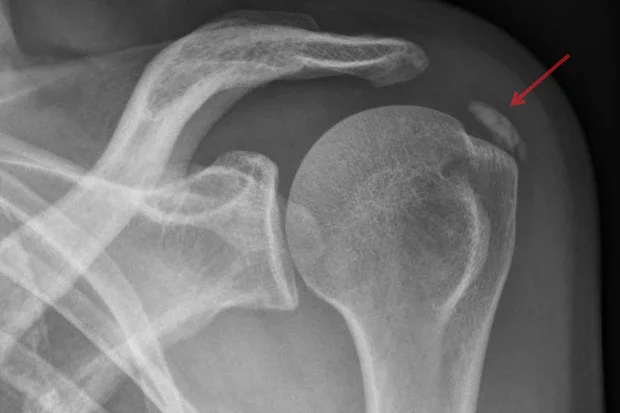

Калцифициращ тендинит на рамото, представлява състояние, което се характеризира с поява на калциеви отлагания в сухожилията на мускулите, изграждащи ротаторния маншон. Най-често се засяга сухожилието на м. супраспинатус. Това води до поява на значителна болка и намален обхват на движение в рамото. Диагнозата се поставя най-често чрез рентгенография,която показва калциеви отлагания на мястото на прикрепване мускулите на ротаторния маншон за раменната кост. Началното лечение е консервативно и включва нестероидни противовъзпалителни средства, физиотерапия, инжектиране на кортикостероиди и перкутанна иглена аспирация. При не повлияване от консервативна терапия се препоръчва оперативно лечение.

Диагнозата калцифициращ тендинит на рамото се поставя въз основа на характерната клинична картина, подробен физикален преглед и образни изследвания, като:

По време на формиращата фаза, рентгеновите изображения обикновено разкриват калциеви отлагания с равномерна плътност и ясен ръб. В по-болезнената резорбтивна фаза, отлаганията изглеждат мътни и с неясни ръбове. При артроскопия, отлаганията във формиращата фаза изглеждат кристални и подобни на тебешир, докато отлаганията в резорбтивната фаза изглеждат гладки, наподобяващи паста за зъби. Ултразвукът също се използва за локализиране и оценка на калциеви отлагания. Във формиращата фаза отлаганията са хиперехогенни и с дъгообразна форма, а в резорбтивната фаза отлаганията са по-малко ехогенни и изглеждат фрагментирани.